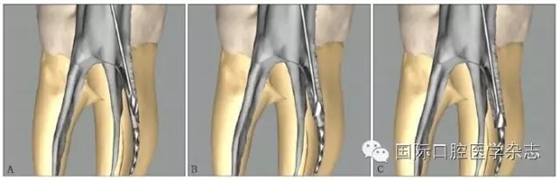

3.2.4 器械材質(zhì)類型的評估 不銹鋼K銼取出的概率略高于鎳鈦機(jī)用器械,這或許是因2類器械的錐度、橫截面設(shè)計和使用方法的截然不同所致。機(jī)用器械多為大錐度,在其旋轉(zhuǎn)運(yùn)動時,器械尖端更易鎖入根管壁。一般情況下,分離的鎳鈦器械較不銹鋼器械更難從根管中取出[14],原因包括以下幾點(diǎn):1)鎳鈦器械為旋轉(zhuǎn)運(yùn)動,更傾向于嵌入根管壁內(nèi)而難以取出[3];2)尤其在使用超聲的情況下,鎳鈦器械因溫度升高容易發(fā)生二次分離[15];3)由于鎳鈦器械有良好的可彎曲性能,分離于彎曲根管中的鎳鈦器械往往抵在根管的外側(cè)壁上而不是保留在根管的中心,增加了取出的難度[16](圖7);4)一般分離器械越長,越容易取出,因?yàn)檩^長的分離器械往往位于根管的更冠方部位,而分離的鎳鈦器械往往較小[17]。

圖 7 分離于彎曲根管的鎳鈦器械往往抵在根管外側(cè)壁,而不會保留在根管的中心

3.2.5 取出難度評估 多數(shù)情況下,如果分離器械上1/3能夠暴露,通常能夠取出。位于直根管、近根管口的分離器械較位于彎曲根管的器械容易取出。位于根管通暢部分的分離器械通常可以取出。如果分離器械位于根管彎曲附近,并且牙本質(zhì)厚度容許建立從根管口到器械冠方的通道以接近其冠部末端,而不至于產(chǎn)生穿孔等并發(fā)癥,則仍有可能將其取出。在這些病例中,都必須建立到達(dá)分離器械上部的直線通路。如果器械分離于彎曲根管的根尖部,則很難建立安全的通道,且分離器械移動可能造成器械超出根尖孔,風(fēng)險較大,通常不太可能將其去除(圖8)。

A:分離器械位于較直的根管中上部分,較容易取出;B~D:分離器械位于根管彎曲之下或彎曲根管近根尖部,無法取出。

圖 8 取出難度的評估